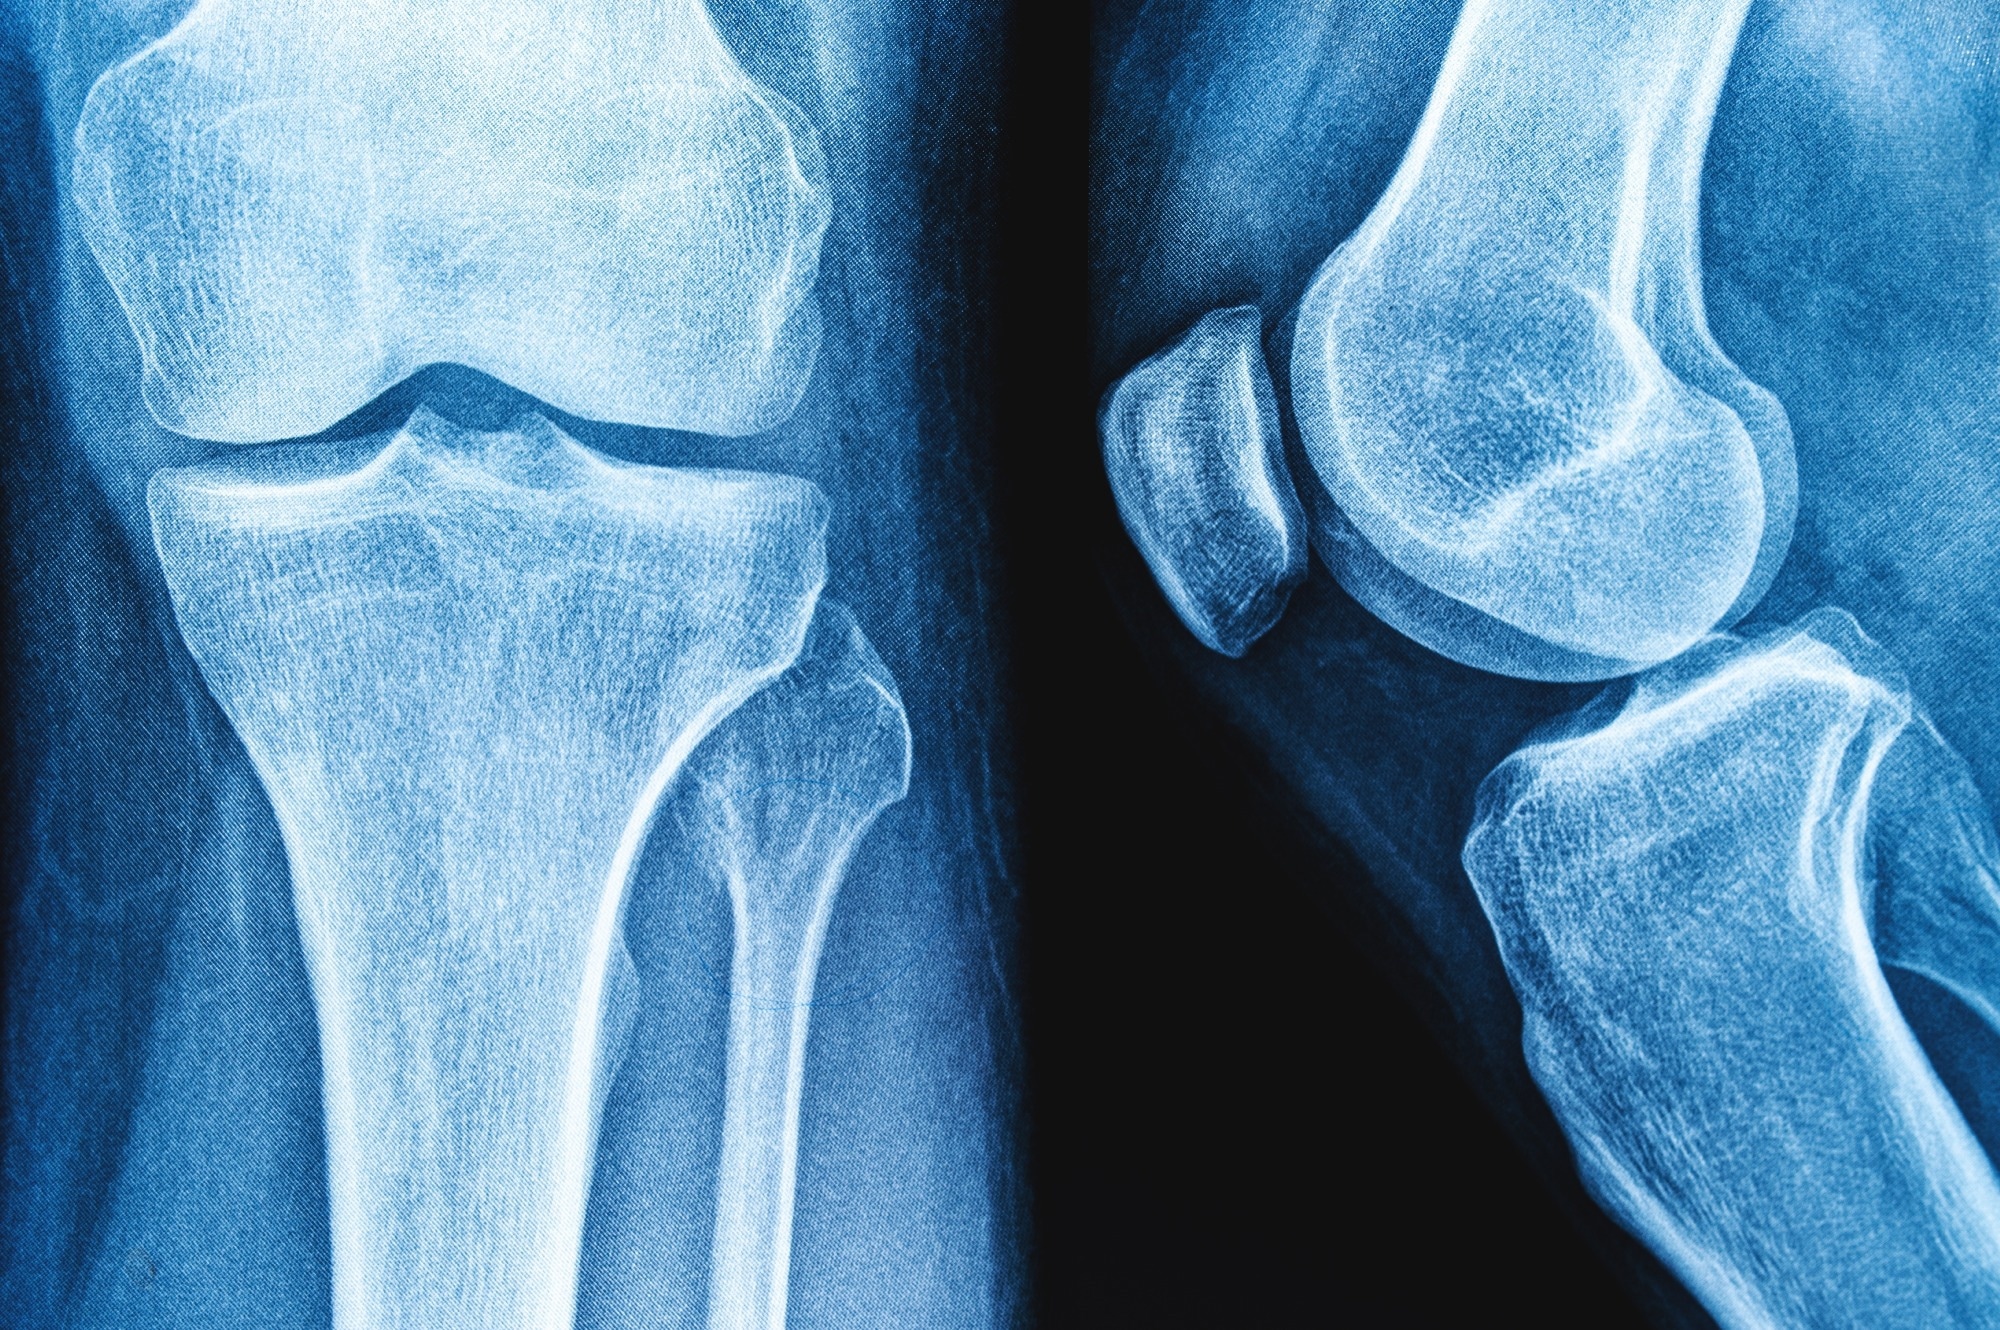

Study: Bone Health After Exercise Alone, GLP-1 Receptor Agonist Treatment, or Combination Treatment. ​​​​​​​Image Credit: siamionau pavel / Shutterstock​​​​​​​Study: Bone Health After Exercise Alone, GLP-1 Receptor Agonist Treatment, or Combination Treatment. ​​​​​​​Image Credit: siamionau pavel / Shutterstock